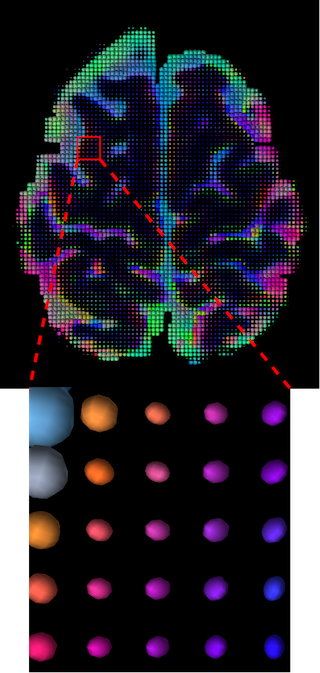

III-D Qualitative Results

The visualization of inpainted results (showing the whole diffusion tensor for each voxel) generated from different models are demonstrated in Figure 3, where the tensor is represented in RGB coding that colours red, green and blue represent diffusion in the x, y, and z axes respectively. One typical example of reconstruction in the disrupted ROIs has been zoomed for visualization. Compared to the ground truth, TW-BAG is able to generate more distinct orientations following the original distribution and intensity across sagittal, coronal and axial views, which could demonstrate water diffusivity (denoted by eigenvalues of tensor model) more accurately. As indicated in Figure 4, the boundaries and textures of the FA map for TW-BAG are less blurry than the other competing models, validating the effectiveness of TW-BAG from a neuroscience perspective.